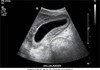

cystic duct image

Coronal decubitus view. The cystic duct seems to arise from the neck of the gallbladder (GB) (arrows). AO, aorta; IVC, inferior vena cava; PV, portal vein; L, liver.